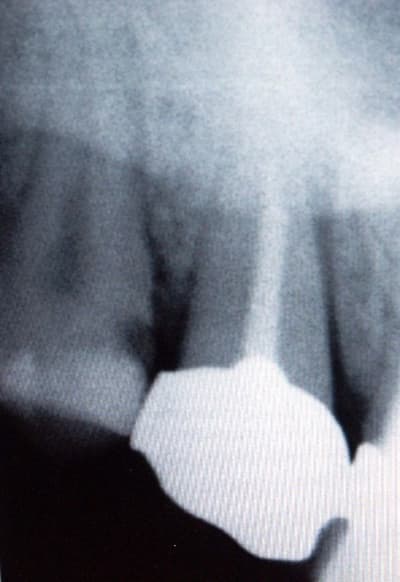

La radio montre un élargissement du desmodonte en mésial et une obturation à mi canal (dent dévitalisée depuis 20 ans). Au niveau apical, la RVG (capteur RSV que je trouve pas top du tout) ne met pas clairement en évidence une pathologie périapicale.

Comme promis, voilà les radios que je vous fournis en dossier attaché.

En les revoyant je n'avais pas trop prété au débord de la couronne ne distal et au début de récidive de carie sous la couronne, d'où perte d'étancheité et problème endo consécutif.

En plus il ya l'air d'avoir un tenon sympa à démonter...

D'ailleurs entre les deux RX, on note un élargissement ligamentaire en mésial de 17 qui montre que la douleur provient bien de cette dent.